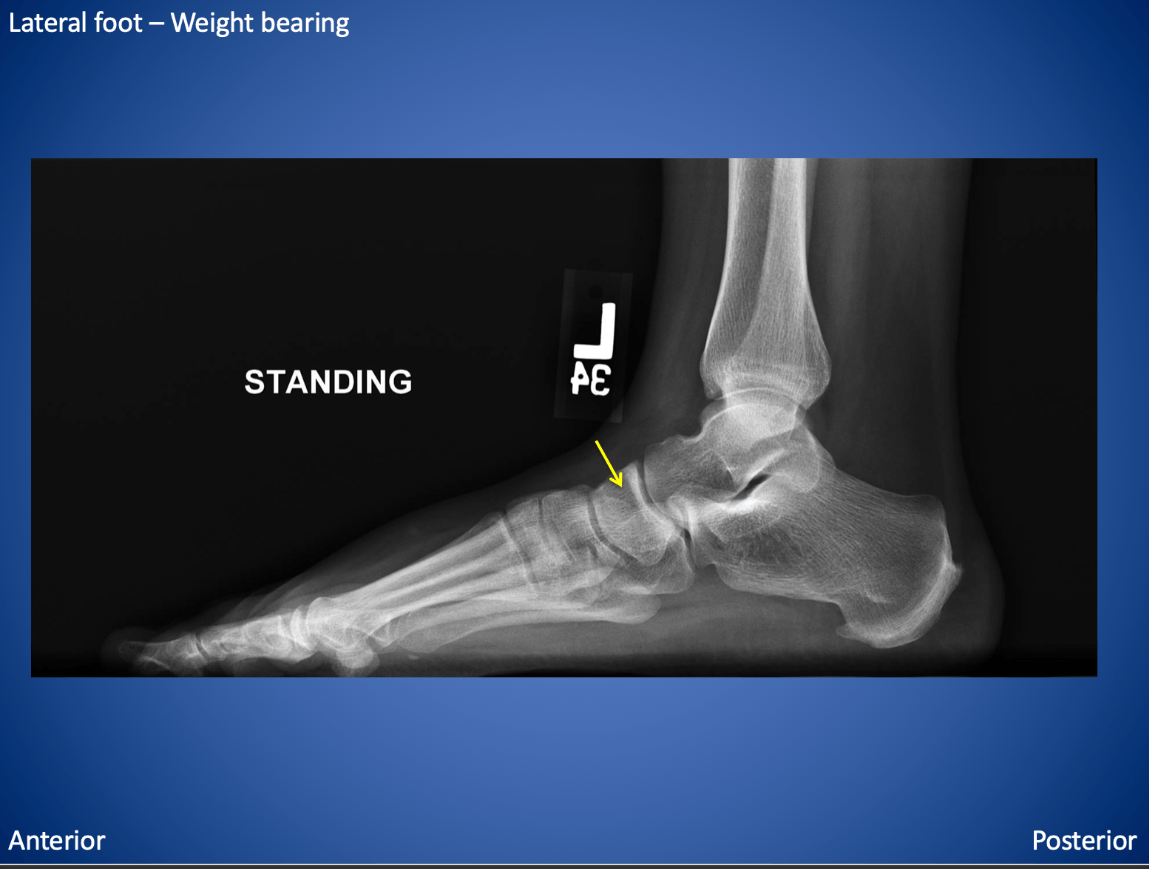

The yellow arrow points to this tarsal bone.

What is the navicular?